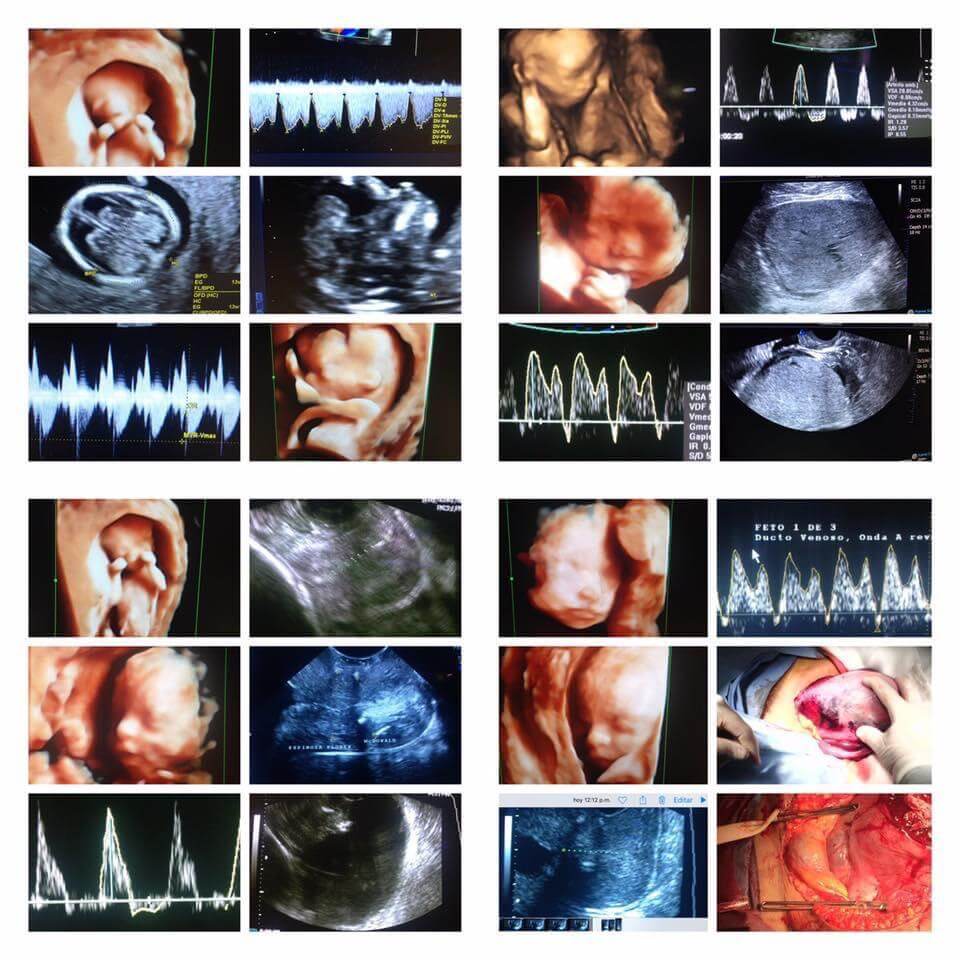

Realiza tamizaje de Síndrome de Down (primer trimestre), alteraciones estructurales (segundo trimestre) y vigilancia del crecimiento (tercer trimestre) a través de Ultrasonido de alta definición, Doppler, 3 y 4 dimensiones. Predicción, prevención y tratamiento especializado de Preeclampsia, parto pre-termino, diabetes gestacional y manejo de enfermedades crónicas durante el embarazo.

con ultrasonido de alta especialidad, Genético 11-14 semanas (detección de síndrome de Down y predicción de riesgo de Preeclampsia), Estructural 18-24 semanas (Anatomía fetal, prevención de parto pretérmino), Crecimiento, 3-4D, embarazo gemelar y doppler.

DNA fetal en sangre materna y estudios Cariotipo.

para mamás antecedentes de Preeclampsia y Sangrado. Enfermedades Crónicas en el embarazo: Diabetes, Hipertensión, Lupus, Síndrome de anticuerpos antifosfolipidos, enfermedad renal o cardiaca. Cirugía obstétrica de alta complejidad: Acretismo, cerclajes, placenta previa, miomas y embarazo.